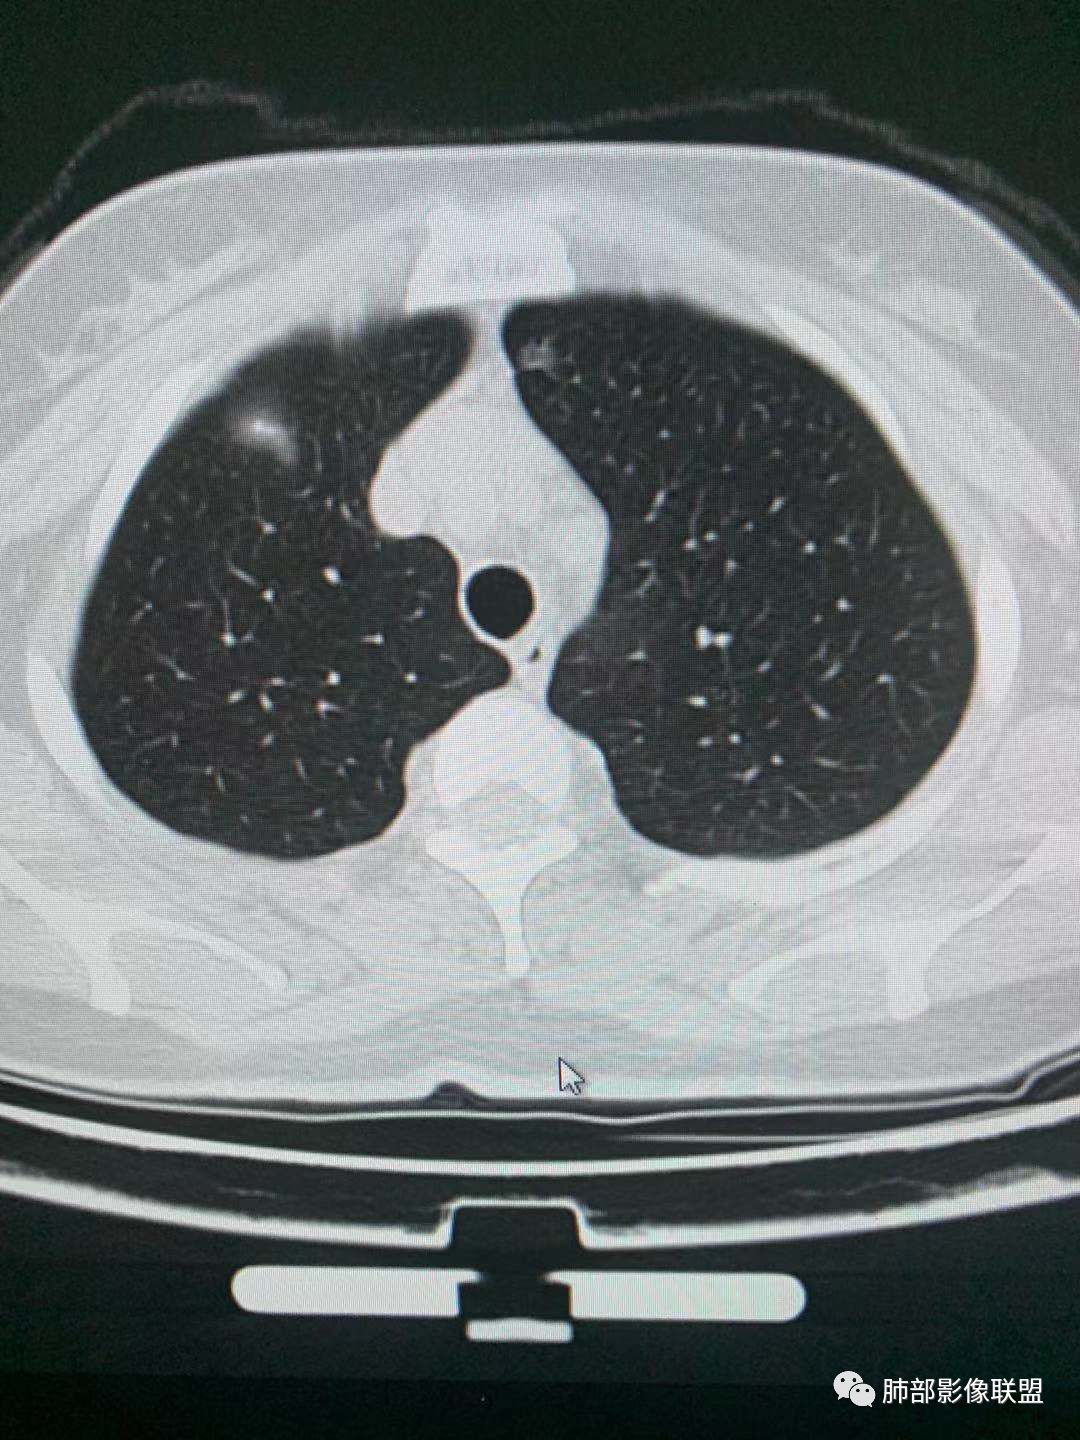

二、看第二个结节

1、密度?

2、边界?

3、收缩力?

4、血管?

5、大小、内部结构、CT值

金豆

纯磨玻璃 边界清

小兜

三个石头

纯磨玻璃,能画出轮廓,但是感觉边缘又比较模糊,是层厚原因吗,收缩力弱,血管进入

心灵鸡汤

与左肺上叶纵隔旁pGGN

南边

三、看看这一个

1、密度:PGGN?MGGN?

lmg

这个密度要高一些,混合磨玻璃结节

MGGN,比上面两个密度高

这个结节中间密度稍高一些 不像纯的

都认为mggn,都觉得密度高了?

三.右肺上叶胸膜下结节及左肺上叶血管旁结节,尽管都是磨玻璃密度,但都比较小且边缘特征不明显,恶性征象未显露,处置并无特殊,定期复查!